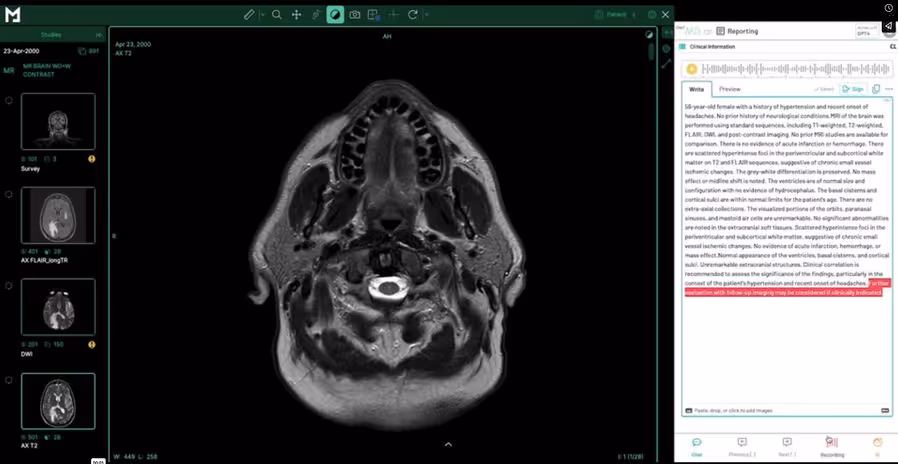

Synchronized browser windows allow radiologists to view imaging studies while completing structured reports side by side, ideal for remote reporting or busy hospital environments.

Radiologists and clinical collaborators can access and review imaging studies side-by-side with structured reports using synchronized browser windows. Our web-based reporting interface integrates directly with our diagnostic viewer, enabling real-time visualization and reporting from anywhere.